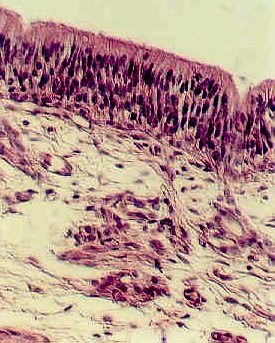

The stratified squamous epithelium signals that you are in the True Vocal Cord. The photograph to the left illustrates the epithelium. Move deeper under this epithelium. You will first encounter dense connective tissue. This is the Vocal Ligament. Continue to follow this tissue to a mass of muscle cut in cross section. This is the Vocalis muscle. It is illustrated in the photograph, below.